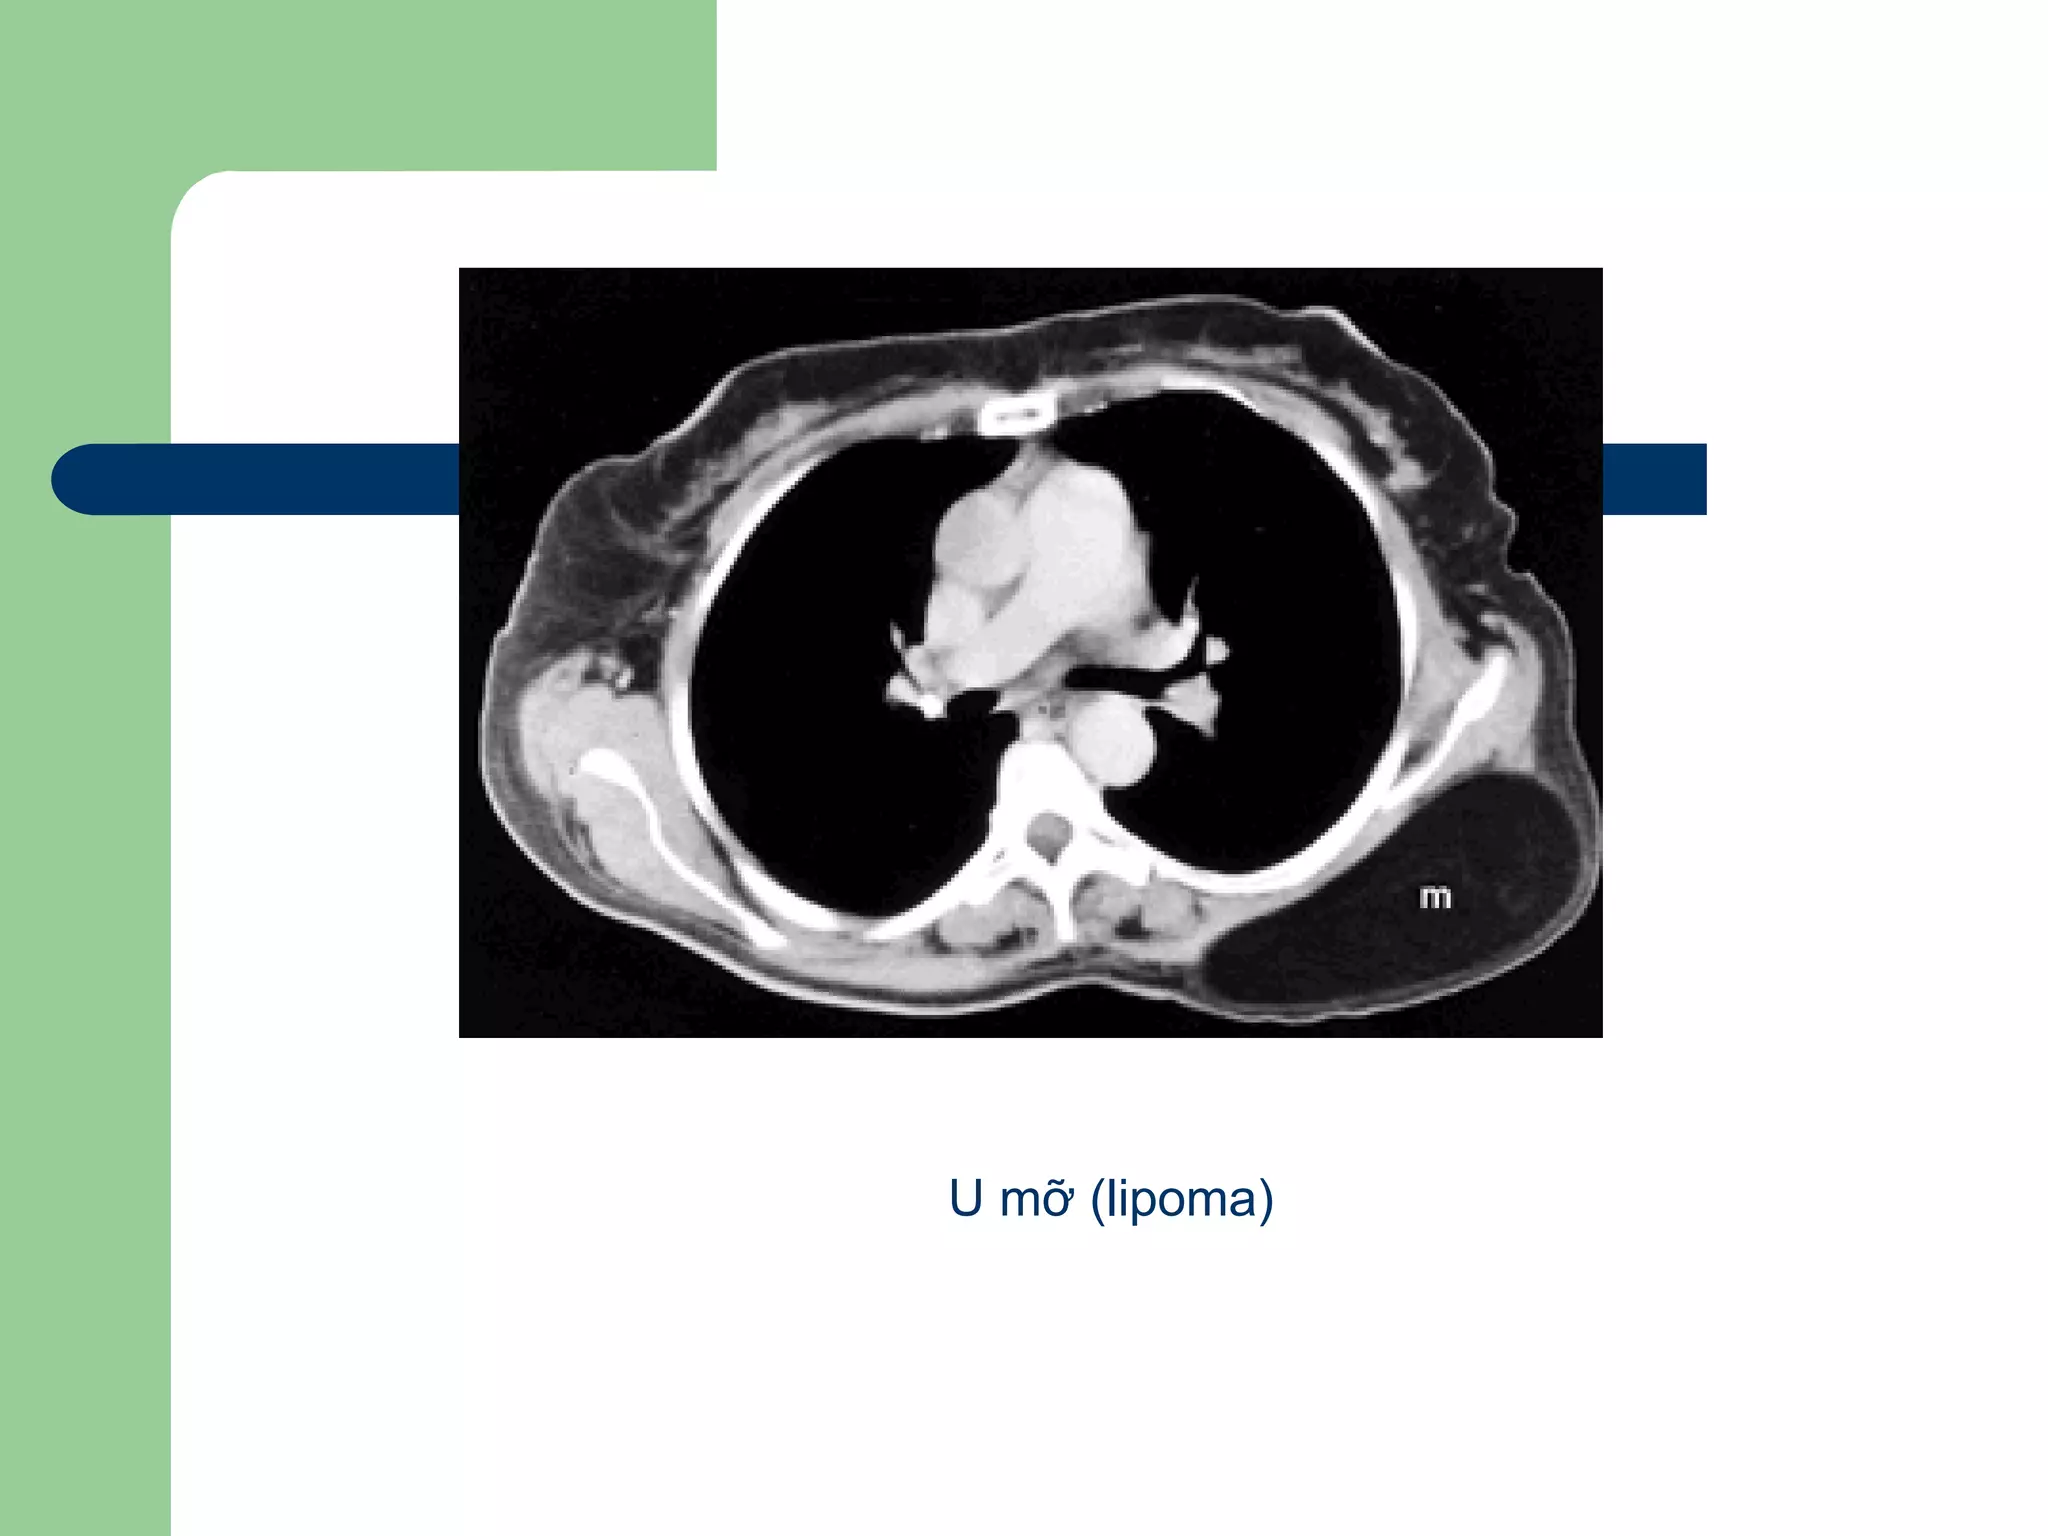

U phổi lành tính

 Lipoma

U trung thất

 CT đánh giá u về vị trí, kích thước, đè đẩy

xâm lấn các cấu trúc khác: mạch máu, khí

phế quản, thành ngực, bản chất mô học

(#68%) (lipoma, cyst…)

U mỡ (lipoma)

U phổi lànhtính  Hamartoma  Lipoma  Fibroma  Leiomyoma  Neurofibroma  Hạch trong phổi